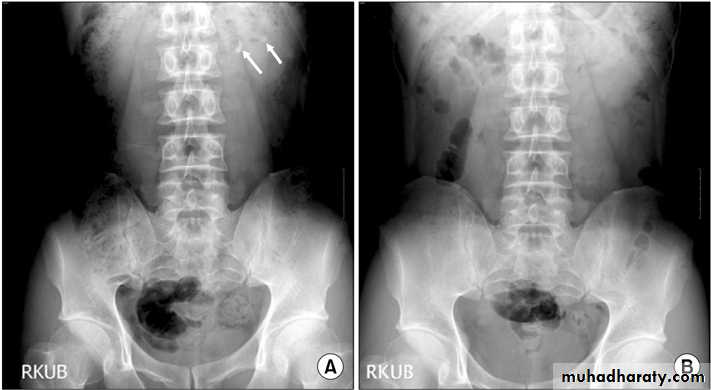

Urinary calculi

Nephrocalcinosis